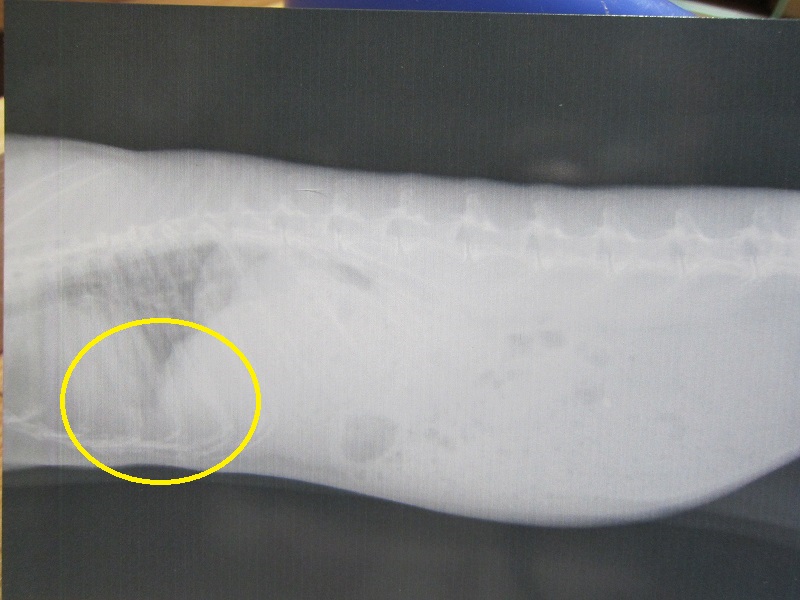

で、レントゲン。

前回記事で印を付けてる部分に着目して下さい。

また、霧が積もってるような感じになってます。

撮影前に、私予想として伝えていたのですが、ほぼ当たり。

リンパ腫は再燃しており、ちょうど、最初、退院して1週間後に撮影した

レントゲンの具合と似た感じ、少しマシ? ぐらいのレベル。